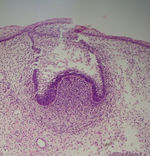

Tooth development is commonly divided into the following stages: the bud stage, the cap, the bell, and finally maturation. The staging of tooth development is an attempt to categorize changes that take place along a continuum; frequently it is difficult to decide what stage should be assigned to a particular developing tooth. This determination is further complicated by the varying appearance of different histologic sections of the same developing tooth, which can appear to be different stages.

The first signs of an arrangement of cells in the tooth bud occur in the cap stage. A small group of ectomesenchymal cells stops producing extracellular substances, which results in an aggregation of these cells called the dental papilla. At this point, the tooth bud grows around the ectomesenchymal aggregation, taking on the appearance of a cap, and becomes the enamel (or dental) organ. A condensation of ectomesenchymal cells called the dental follicle surrounds the enamel organ and limits the dental papilla. Eventually, the enamel organ will produce enamel, the dental papilla will produce dentin and pulp, and the dental follicle will produce all the supporting structures of a tooth.

Bell stage

The bell stage is known for the histodifferentiation and morphodifferentiation that takes place. The dental organ is bell-shaped during this stage, and the majority of its cells are called stellate reticulum because of their star-shaped appearance. Cells on the periphery of the enamel organ separate into three important layers. Cuboidal cells on the periphery of the dental organ are known as outer enamel epithelium. The columnar cells of the enamel organ adjacent to the dental papilla are known as inner enamel epithelium. The cells between the inner enamel epithelium and the stellate reticulum form a layer known as the stratum intermedium. The rim of the dental organ where the outer and inner enamel epithelium join is called the cervical loop. In summary, the layers in order of innermost to outermost consist of dentine, enamel (formed by inner enamel epithelium, or 'ameloblasts', as they move outwards/upwards), inner enamel epithelium and stratum intermedium (specialised stratified cells that support the synthetic activity of the Inner Enamel Epithelium) What follows is part of the initial 'enamel organ', the middle of which is made up of stellate reticulum cells. This is all encased by the outer enamel epithelium layer.